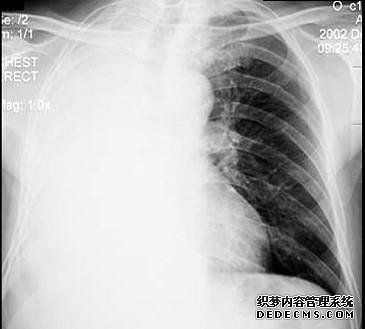

右中叶小结节右下斜0.5 cm斜小胸膜小mi巢现在胸部

父亲的胸部X光片显示了肺中的结节。戒烟的习惯是什么?是肺癌吗?如果没有血液,他通常不会咳嗽。